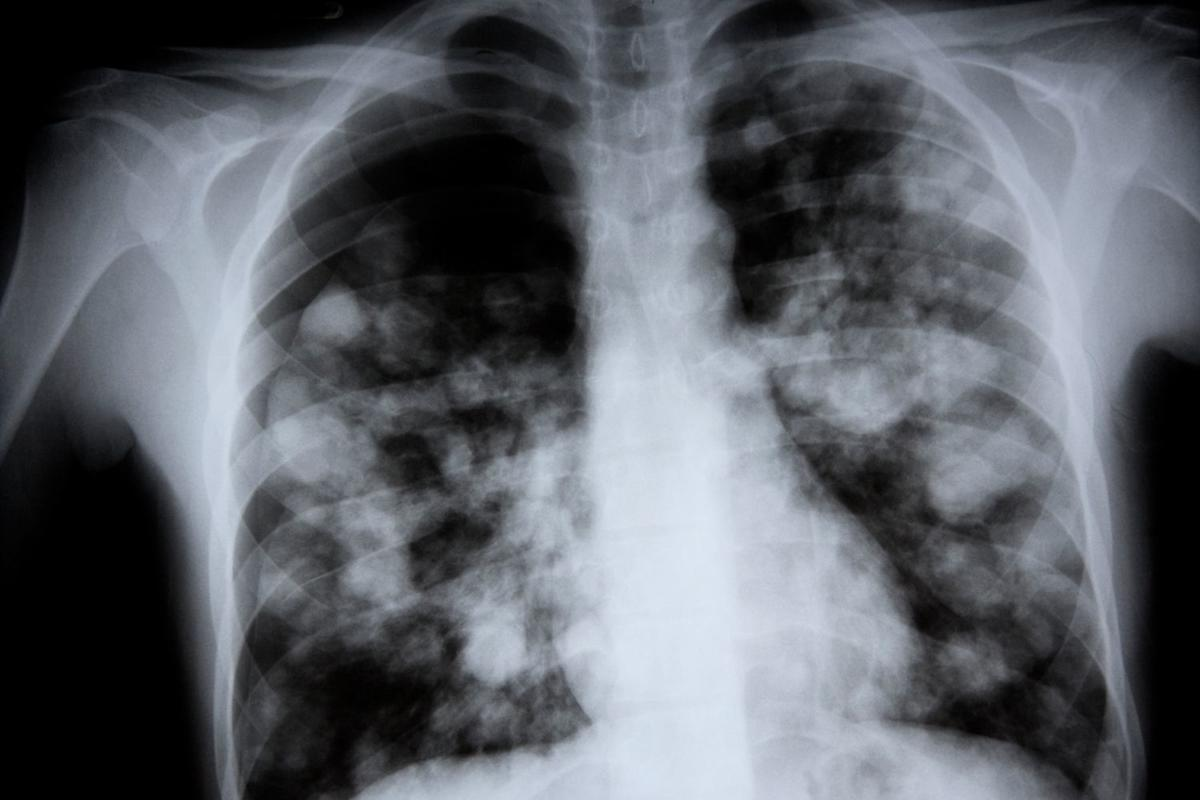

Pneumonia is a complex condition caused by different pathogens. It’s important to know how it spreads to prevent it and manage it well.

Pneumonia can be caused by various pathogens. Bacterial pneumonia is often caused by Streptococcus pneumoniae. Viral pneumonia can be caused by influenza viruses or respiratory syncytial virus (RSV). Fungal pneumonia is more common in people with weakened immune systems.